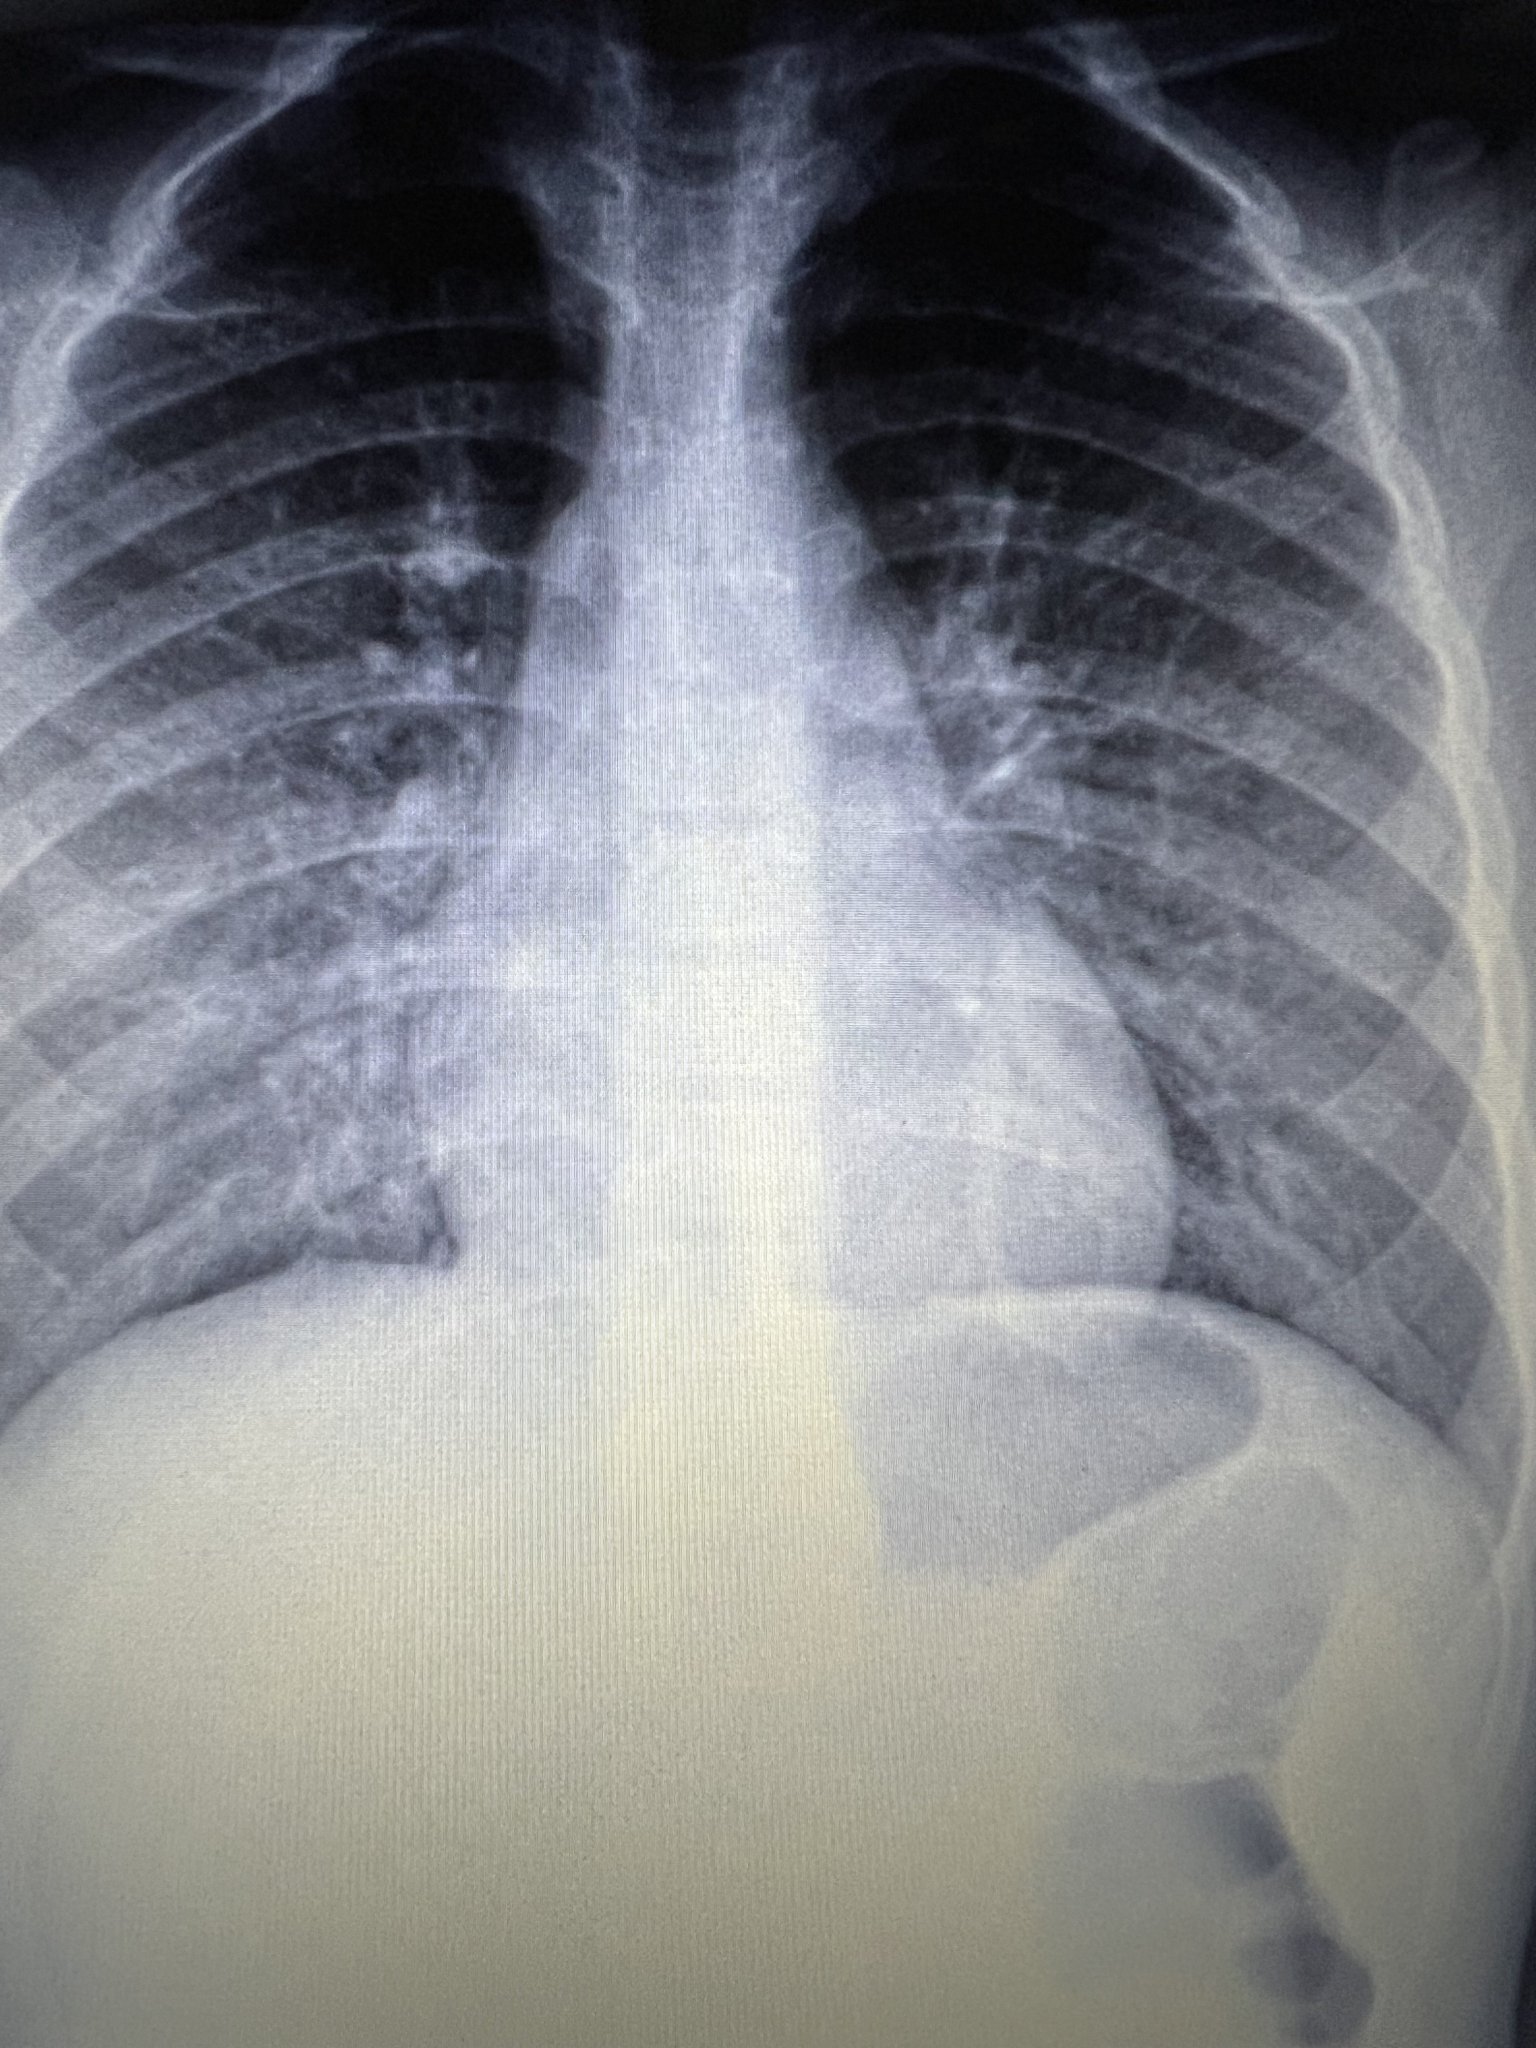

Здравейте, д-р Янкова! Ще може ли да коментирате рентгеновата снимка на сина ми, която е правена след изкаран Ковид и Грип А. Снимката е правена на 26 януари и пи АБ до преди 10 дни, но от два дни детето е с температура около 37-37,7, слаба кашлица, хрема и нощно изпотяване и треска при ниска Т около 37 градуса. Целият става мокър вечер. Вчера му пуснахме изследвания, които според мен (до колкото разбирам) говорят за бактериална инфекция. Ще ви прикача рентгена и изследванията. Моля Ви за съвет, защото вече се виждам в чудо с това болно дете от 1 месец! Притеснява ме да не би да е бил с пневмония и да не се е доизлекувал...... т.е. да не е разчетена правилно снимката, а ме е страх за няма месец да го снимам два пъти. АБ беше Клацид от 250 за 7 дни.

Здравейте, на снимката и изследванията няма нищо притеснително. Всички тези оплаквани и симптоми, които има, са най-вероятно вследствие на постковид синдром. След 2 седмици ще отзвучат.